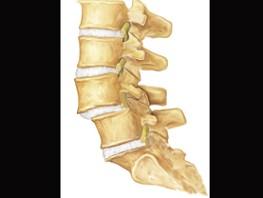

问题 关于腰椎滑脱下列哪项正确 ( )

选项 A、腰椎滑脱手术治疗最关键是滑脱复位与固定 B、腰椎正侧位X线片可清晰显示峡部情况 C、退变性腰椎滑脱常超过Ⅱ° D、峡部型滑脱多无明确的外伤史 E、腰椎滑脱均应积极手术治疗

答案 D